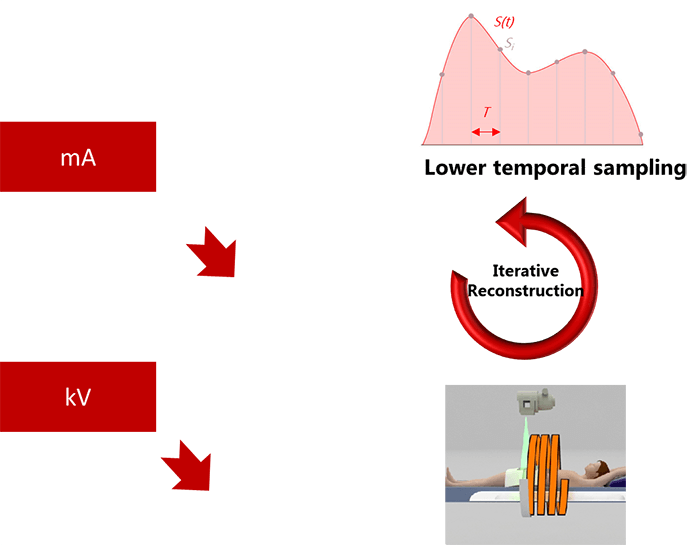

Knowing the fact that the use of CT perfusion imaging is increasing, the need for efficient radiation-reduction strategies is important. In most cases, brain perfusion CT images are acquired with tube currents ranging from 100-200 mAs. This level of radiation produces photons with a mean energy close to the K edge of Iodine, which optimizes the signal-to-noise ratio.

However, with the new technology, a number of strategies have been adopted successfully to lower mA and kV, among which are lower temporal sampling, iterative reconstructions, and increased pitch.